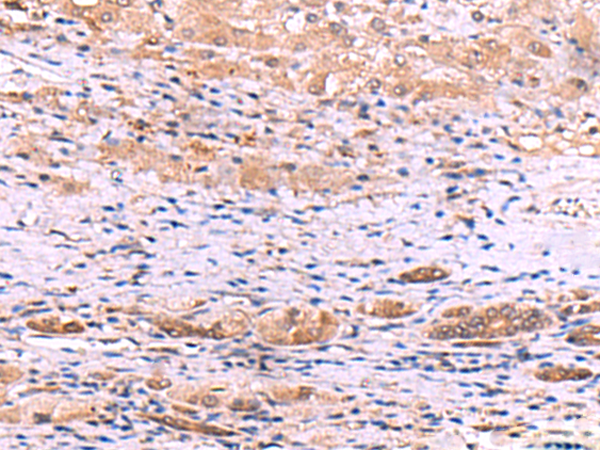

IHC positive control: |

Human liver cancer |

IHC Recommend dilution: |

50-300 |